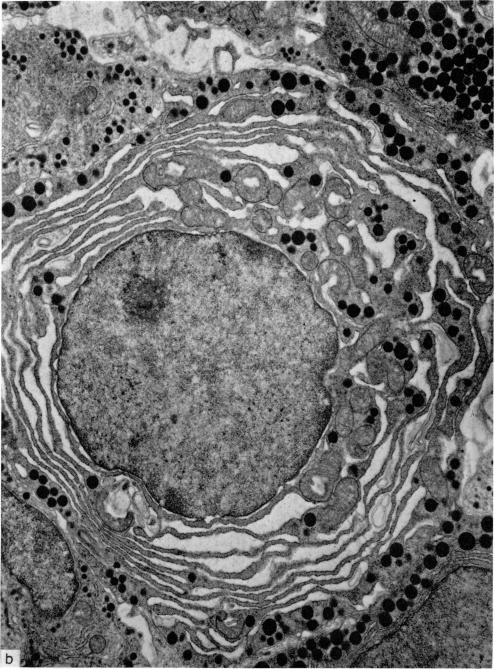

An electron microscopical study has been carried out to evaluate the effect of neonatal thymectomy on the hypophysis of germ-free mice at different times after the operation. The results fully confirm the previous findings in neonatally thymectomized, conventional mice. Also neonatal thymectomy in germ-free mice results in degranulation of growth hormone-producing cells in the anterior pituitary gland. A large number of these cells show an enlarged endoplasmic reticulum with formation of cisternae and loss of hormone granuli. This alteration of growth hormone-producing cells is similar to that observed in other cells of the hypophysis after removal of other target glands such as thyroid or gonads. The changes in the growth hormone-producing cells in neonatally thymectomized germ-free mice occur even in the first days after birth, when the number of differentiated growth hormone-producing cells is still very low. Some thymectomized germ-free mice showed symptoms of the wasting syndrome but the alterations in their hypophysis were not more pronounced than those observed in thymectomized germ-free but nonwasting mice. The data fit well our suggestion that the perinatal thymus is under hypophysial control and that immunological maturation depends on endocrine function.

已进行了一项电子显微镜研究,以评估新生期胸腺切除对无菌小鼠术后不同时间垂体的影响。结果充分证实了先前在新生期胸腺切除的常规小鼠中的发现。同样,无菌小鼠的新生期胸腺切除会导致垂体前叶中产生生长激素的细胞脱颗粒。大量这些细胞显示内质网扩张,形成池状结构,激素颗粒丢失。产生生长激素的细胞的这种改变类似于在切除其他靶腺(如甲状腺或性腺)后垂体其他细胞中观察到的改变。新生期胸腺切除的无菌小鼠中产生生长激素的细胞的变化甚至在出生后的头几天就会出现,此时分化的产生生长激素的细胞数量仍然非常少。一些胸腺切除的无菌小鼠出现了消瘦综合征的症状,但其垂体的改变并不比在胸腺切除的无菌但未消瘦的小鼠中观察到的更明显。这些数据很好地符合了我们的建议,即围产期胸腺受垂体控制,免疫成熟取决于内分泌功能。